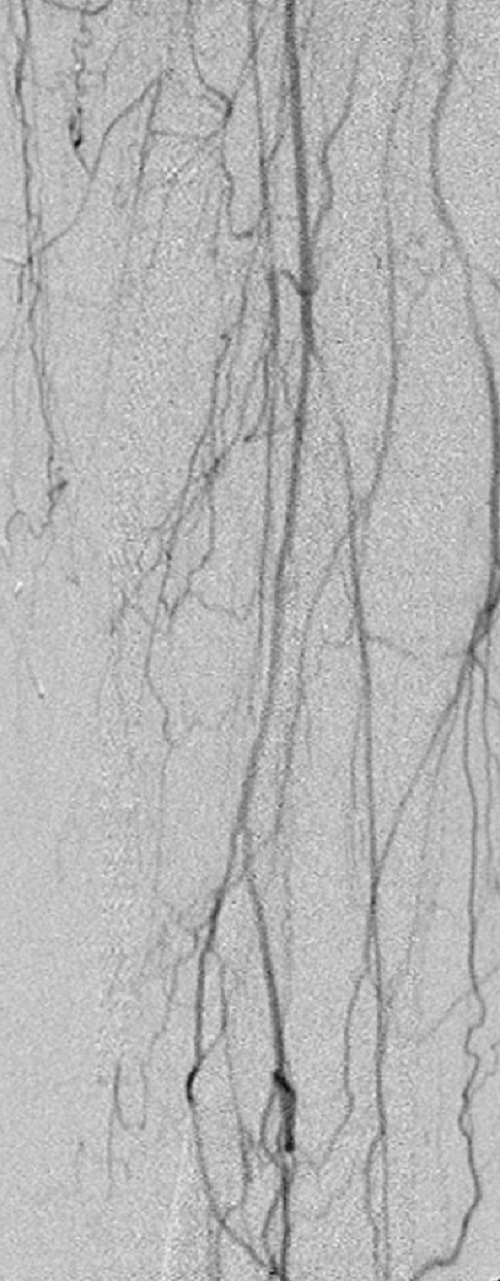

Key to images:

Top panel: Pre-intervention run-off angiogram of the left lower extremity showing, from left to right, irregular left common femoral artery (LCFA) arrowed on the 1st image, absent left superfical femoral artery (LSFA) or any bypass conduit on the 2nd image, sketchy descending collaterals from the left deep femoral (LDFA) that reconstitute a faint shadow of the left popliteal artery, arrowed on the 3rd image. The last 2 images faintly show three-vessel run-off below the left knee. The anterior tibial artery is most opacified, followed by the posterior tibial artery; the peroneal artery peeps through the upper edge of the last image. Note how weakly visible these vessels are due to the poor inflow from above.